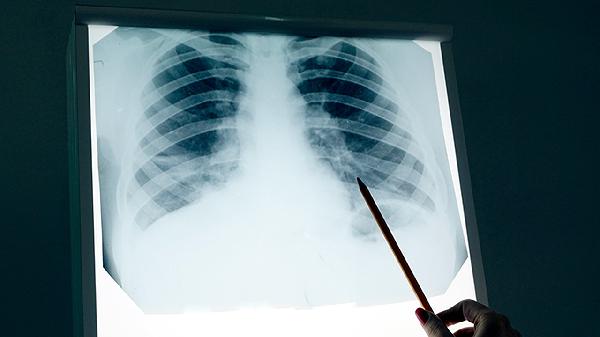

半枝莲可抑制肿瘤血管生成,临床配合放化疗用于肺癌、食管癌患者。该药性寒,脾胃虚寒者慎用,常见剂型有半枝莲胶囊、半枝莲片剂。使用期间需监测肝功能,避免与抗凝药物同服。